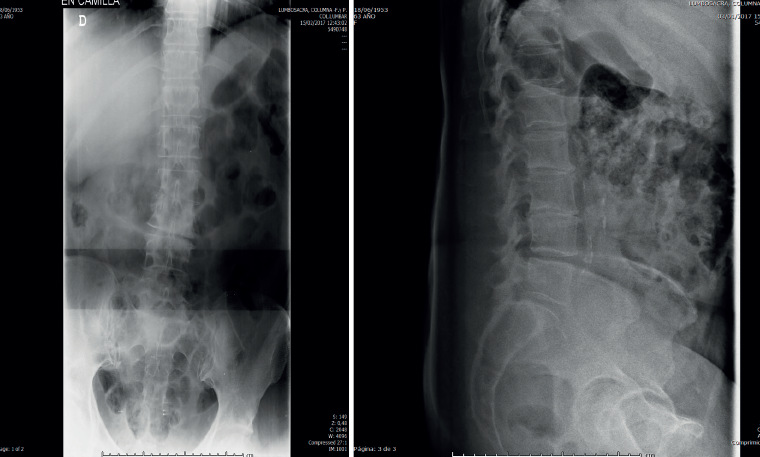

- La radiología simple lumbar (Figura 1) de frente y de perfil muestra grave discopatía L2/L3 con práctica desaparición del disco intervertebral.